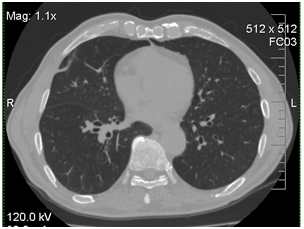

The bronchoscopy and transbronchial biopsy of the lung lesions were performed. Septate mycelium was found by microscopy of the bronchoalveolar lavage (BAL) and lung tissue histology. Abundant growth of moulds was received. The material was sent to the P.Kashkin Research Institute of Medical Mycology at I.Metchnikov North-Western State Medical University for the identification of species. The obtained fungal culture was identified as Acremonium spp. Growth of Acremonium spp culture was also received from the lung tissue samples (Figure 2).